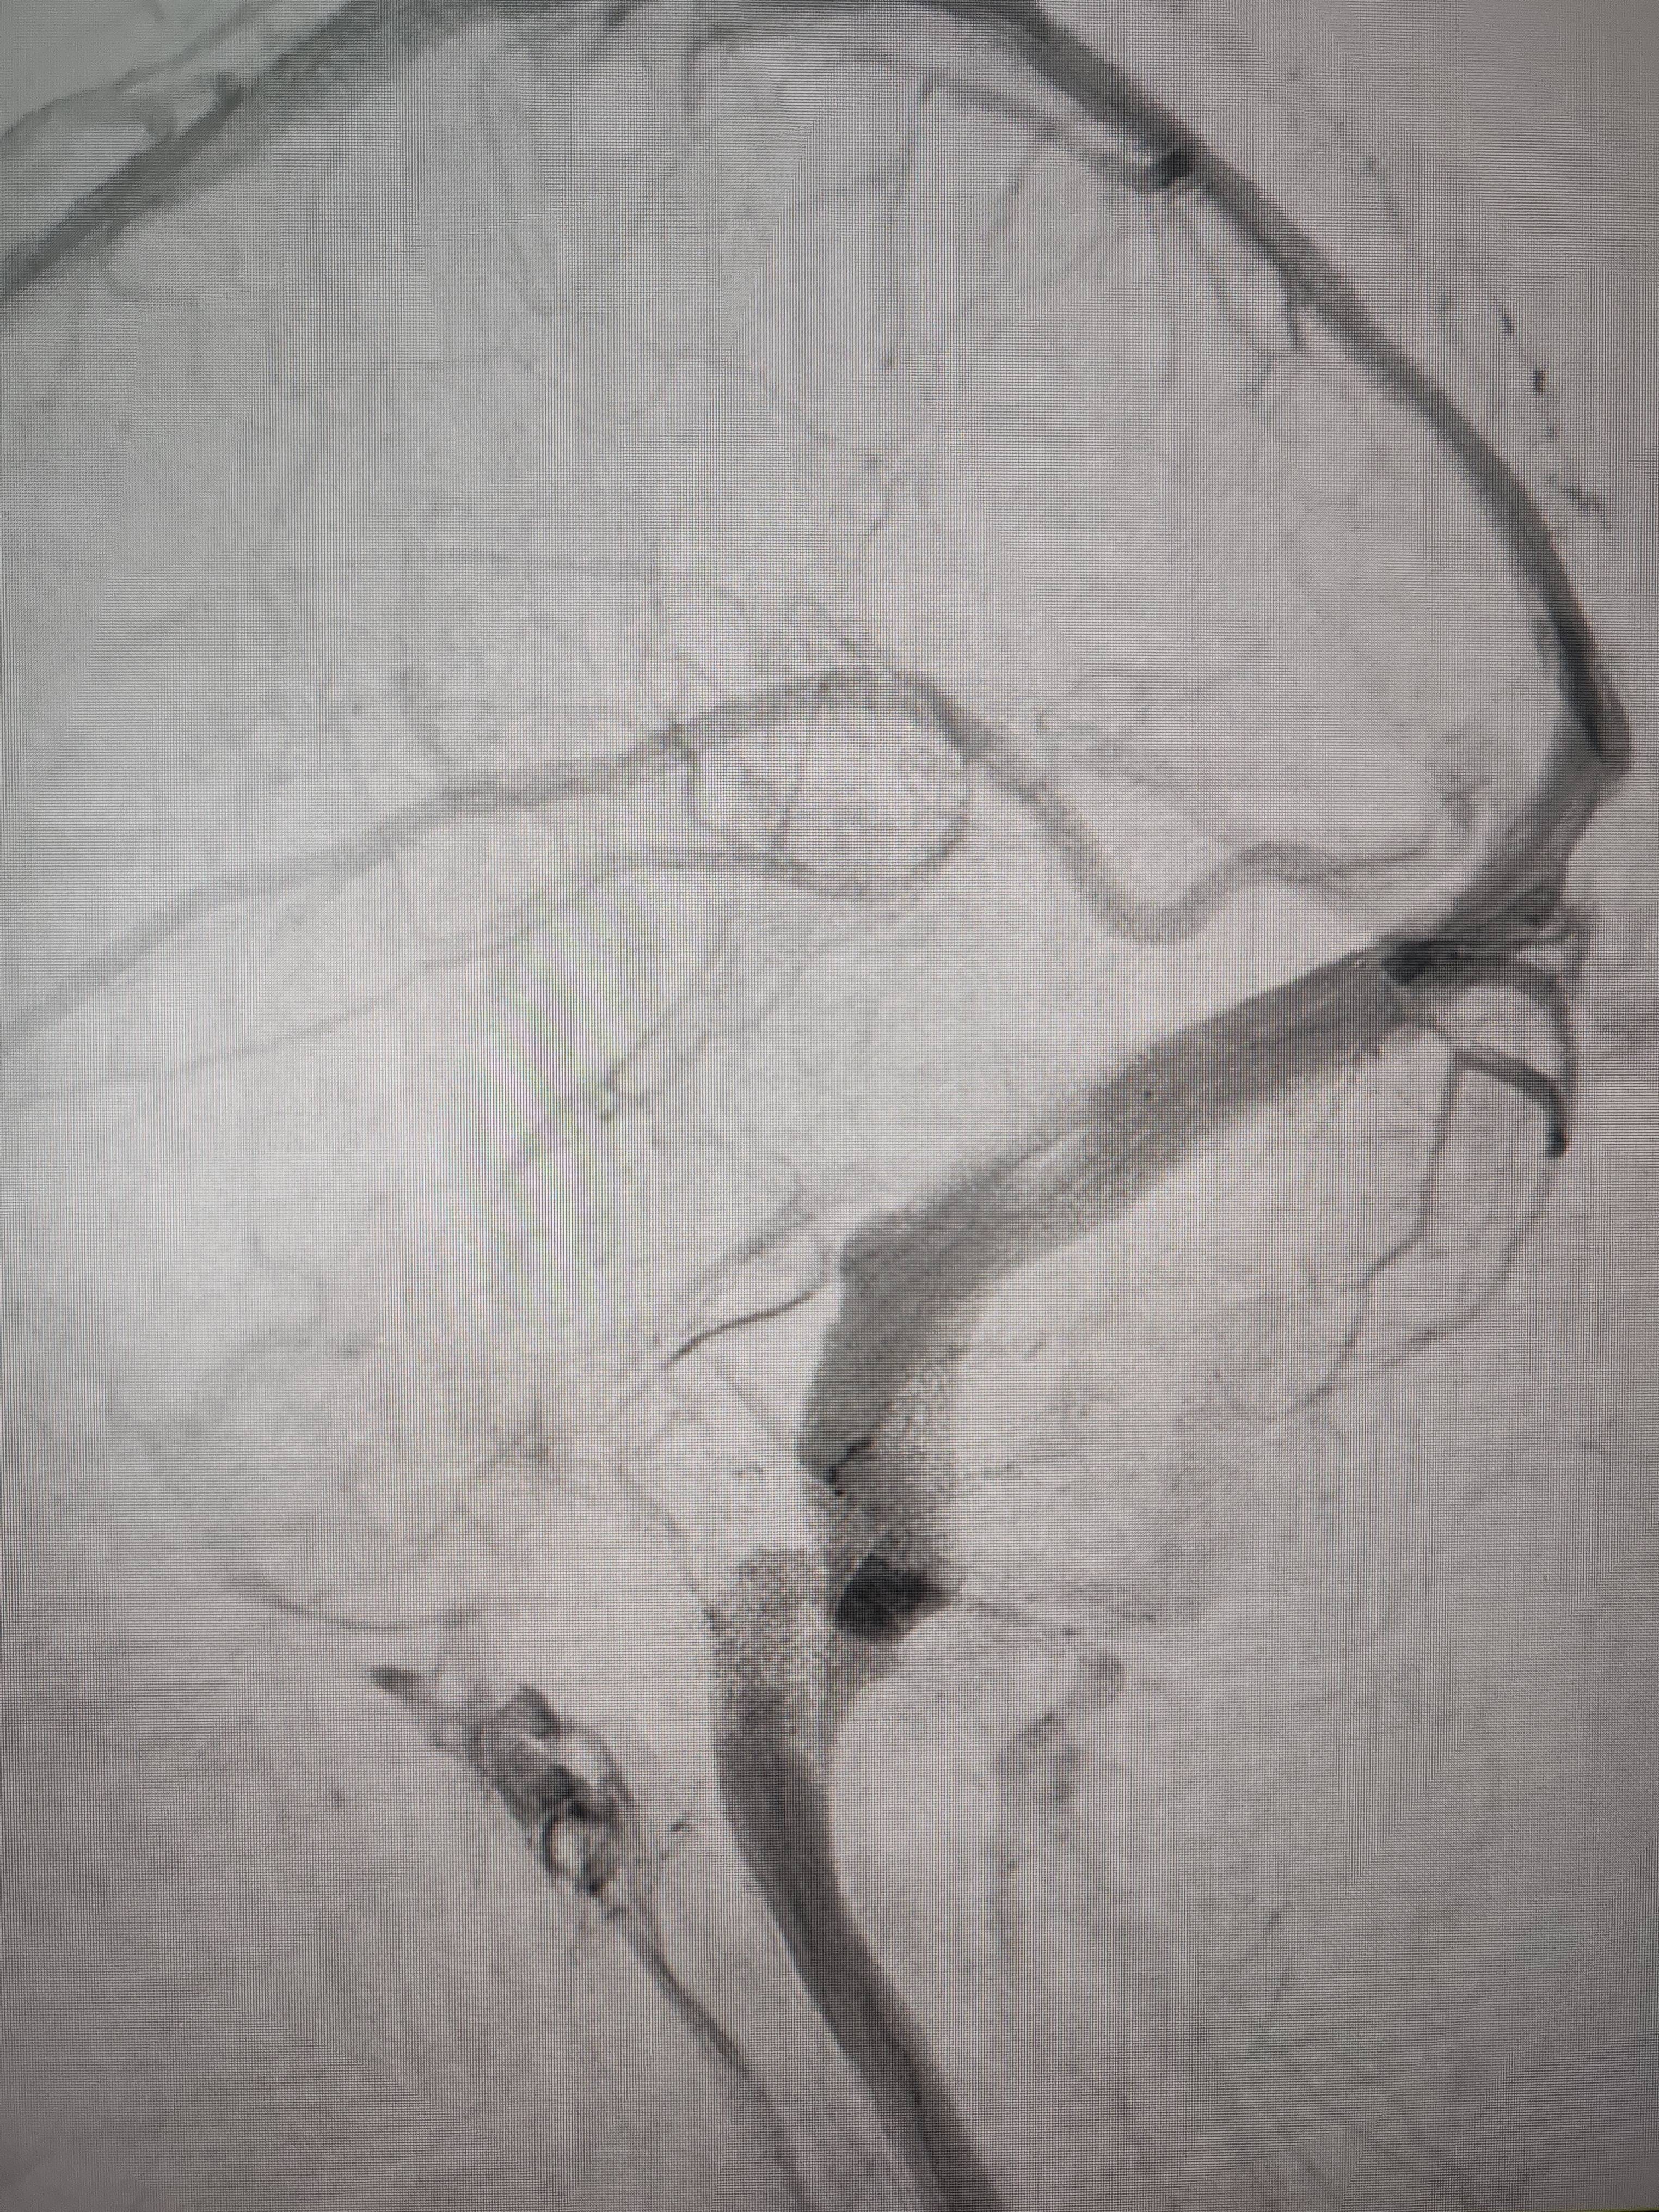

患者造影图像显示,其耳侧静脉窦狭窄idex虚拟币交易所。 南方+ 欧阳少伟 拍摄

李宝民举例说,通过查体、CT、造影等影像技术的检查,患者赵女士是由于静脉窦狭窄,导致缓慢的静脉血流也出现“湍流”现象,其拐弯、打漩涡、回流产生的声响,又顺着骨传导,传至耳蜗处,进而让患者出现搏动性耳鸣的症状idex虚拟币交易所。

经过静脉窦支架置入手术治疗后,患者的静脉窦“堵点”被打通idex虚拟币交易所。 南方+ 欧阳少伟 拍摄